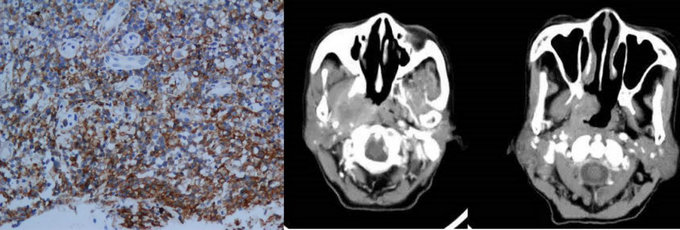

NK/T淋巴瘤病理及影像表現

但是依據Ann Arbor分期,約80%病例為局限期,而這部分局限期患者的治療效果很差,預后不良,說明Ann Arbor分期難以準確反映結外鼻型NK/T細胞淋巴瘤的侵犯程度,對于治療方案的選擇和預后判定價值有限。腫瘤的精準分期是開展合理治療的基礎,尋找更為準確有效的分期系統,成為了目前針對NK/T細胞淋巴瘤進行精準治療的關鍵前提之一。